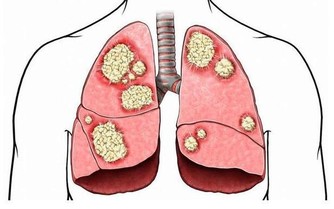

作為人體的排毒器官,肝臟負責將人體的有毒物質分解轉化,當毒素多到肝臟無法分解的時候,就會留在肝臟中,

肝臟中堆積太多的有毒物質勢必會傷害肝細胞,時間久了,肝細胞就會死亡。